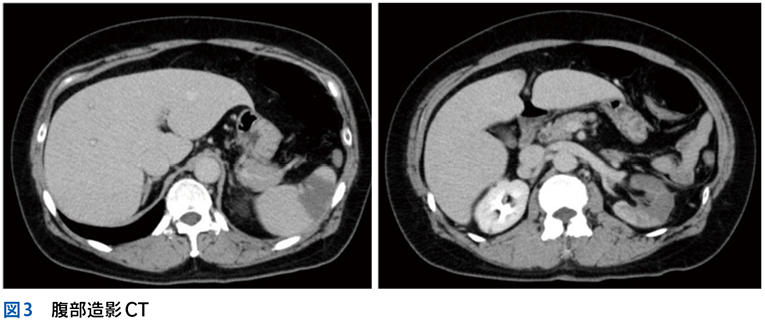

▶ フレームの広さを決めるのは,定義された問題の“yield”である。yieldとは「産み出す」というような意味で,定義された問題がどれほど診断に資するかによって,問題のyieldが高い(high yield),低い(low yield)という使い方をする。high yieldな問題によるフレームは狭く,可能な診断の数を大きく絞り,診断をぐっと近づける。言い換えれば,ある診断(の一群)に対して特異度が高い。一方で,low yieldな問題によるフレームは広く,鑑別診断を意味のある数に絞ることに役立たない(図3)。

▶ 症例によっては,ここまで述べたような条件を満たす問題を複数定義できることがある。この場合は,それぞれの問題が描くフレームが重なり合うところに診断があると考えるとよい(図3)。

▶ 再びNew England Journal of Medicine誌上の症例検討3)を例として挙げる。40歳代男性が急性多関節炎,下腿の結節性紅斑,両側肺門部リンパ節腫脹を呈したケースである。これら3個の問題の組み合わせは,知っていればLöfgren症候群というサルコイドーシスの1病型と「スナップ診断」できるが,この知識がなくてもフレームの重ね合わせで診断に至ることが可能である。

▶ これらの問題はそれぞれが比較的high yieldであり,よいフレームとなりうる。3つのフレーム内でそれぞれ網羅的に鑑別を挙げ(その方法はステップ②で後述),重なるところに着目するとサルコイドーシスが診断の第一仮説に浮上する。ちなみにこのケースでは患者は発熱と失神も呈しているが,発熱はlow yieldであり鑑別を減らすのに役立たず(急性多関節炎,結節性紅斑,肺門部リンパ節腫脹を呈する疾患はほぼすべて発熱を呈してもおかしくない),失神はこのケースでは最終的に(心サルコイドーシスに起因するものではなく)発熱下での神経調節性失神という評価となり,サルコイドーシスの診断においてはノイズだった(二元論で説明される症状だった)ことがわかる(図7)。